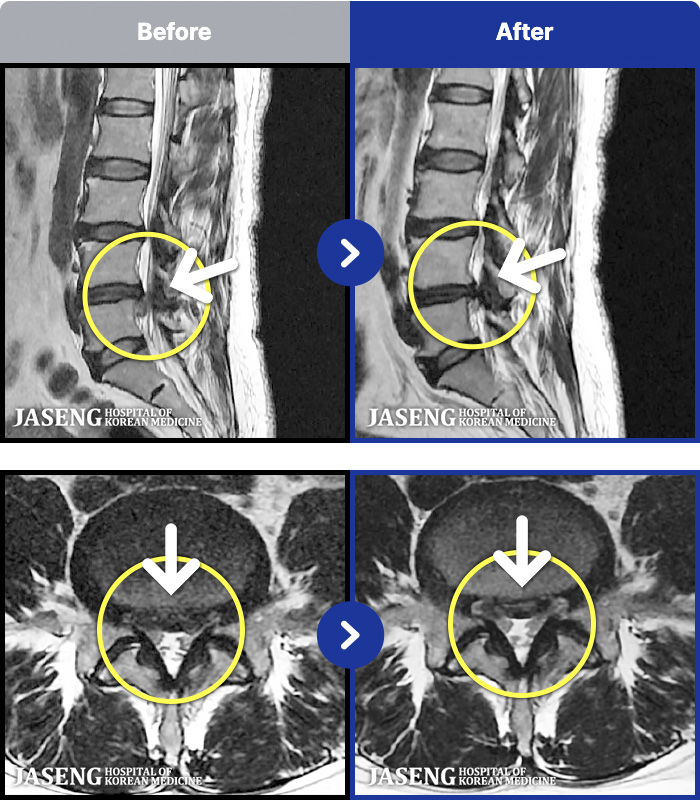

88 MRI ũ ʸ Ȯϼ.